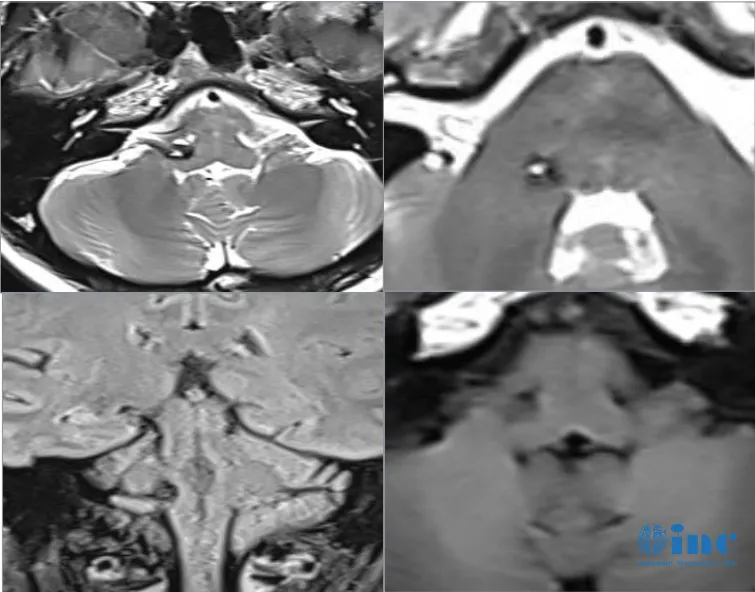

比如31岁的脑干海绵状血管瘤患者陈先生,因出现身体、脸部麻木,还有听力下降、头晕等症状,就诊后怀疑是脑干海绵状血管瘤引起的出血,10多天病情恶化、无法独立行走。

关于目前是否需要尽快手术,巴教授这样评估:

“在核磁共振成像上看到的是新出血。如果我们看T2序列的图像,我们还可以看到周围水肿,这表明出血是新鲜的,对于手术来说,这实际上是手术的好时机。如果再等一两个月,血液会被部分吸收,但疤痕的形成会增加手术的难度。因此,现在是手术的好时机”。点击阅读后续:3个月从“轮椅之上”到奔跑向前——这是一场与时间赛跑的生死竞速